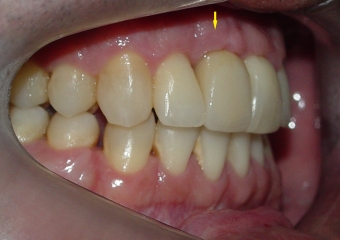

Imagem inicial